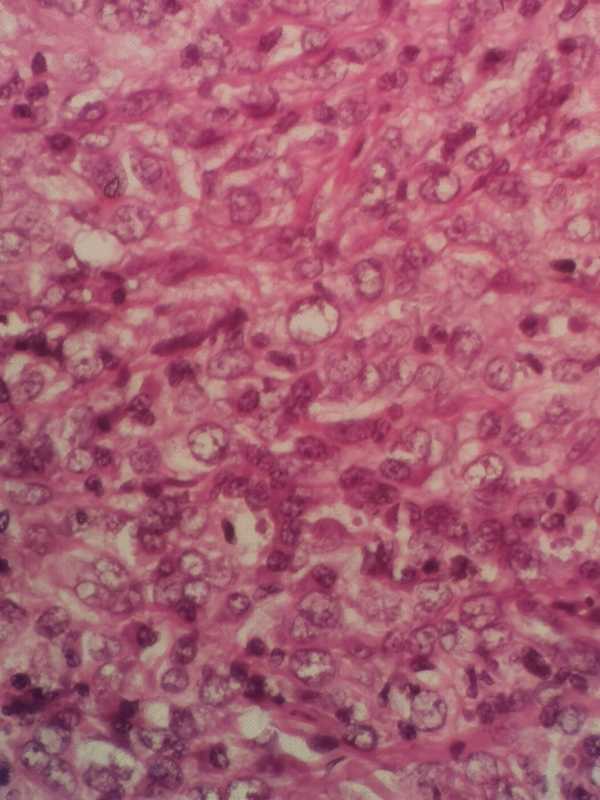

求助各位老师:耳后肿物

性别

男

年龄

64

耳后肿物数年,近来溃破流液

耳后肿物

梭皮一块1.3×0.9×0.5cm,中央皮损区域0.9×0.5,略高出皮表,切面灰粉灰褐 实性 质韧

考虑符合:鳞癌,建议P53.